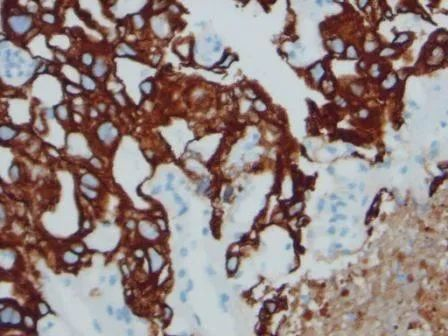

图片

Figure 4. Cited from “Cytokeratin expression in gastrointestinal stromal tumors: morphology, meaning, and mimicry”; The tumor cells are pleomorphic, spindle-shaped and epithelioid, expressing AE1/AE3.

Sarlomo et al. believe that high-risk GIST more frequently expresses AE1/AE3 than low-risk GIST. In their study, the positive rate of AE1/AE3 was 66.7% (8/12). These findings suggest that AE1/AE3 expression in GIST may be a phenomenon related to tumor progression, and AE1/AE3 is common in high-risk GIST; additionally, AE1/AE3 positive expression is also common in metastatic malignant melanoma.